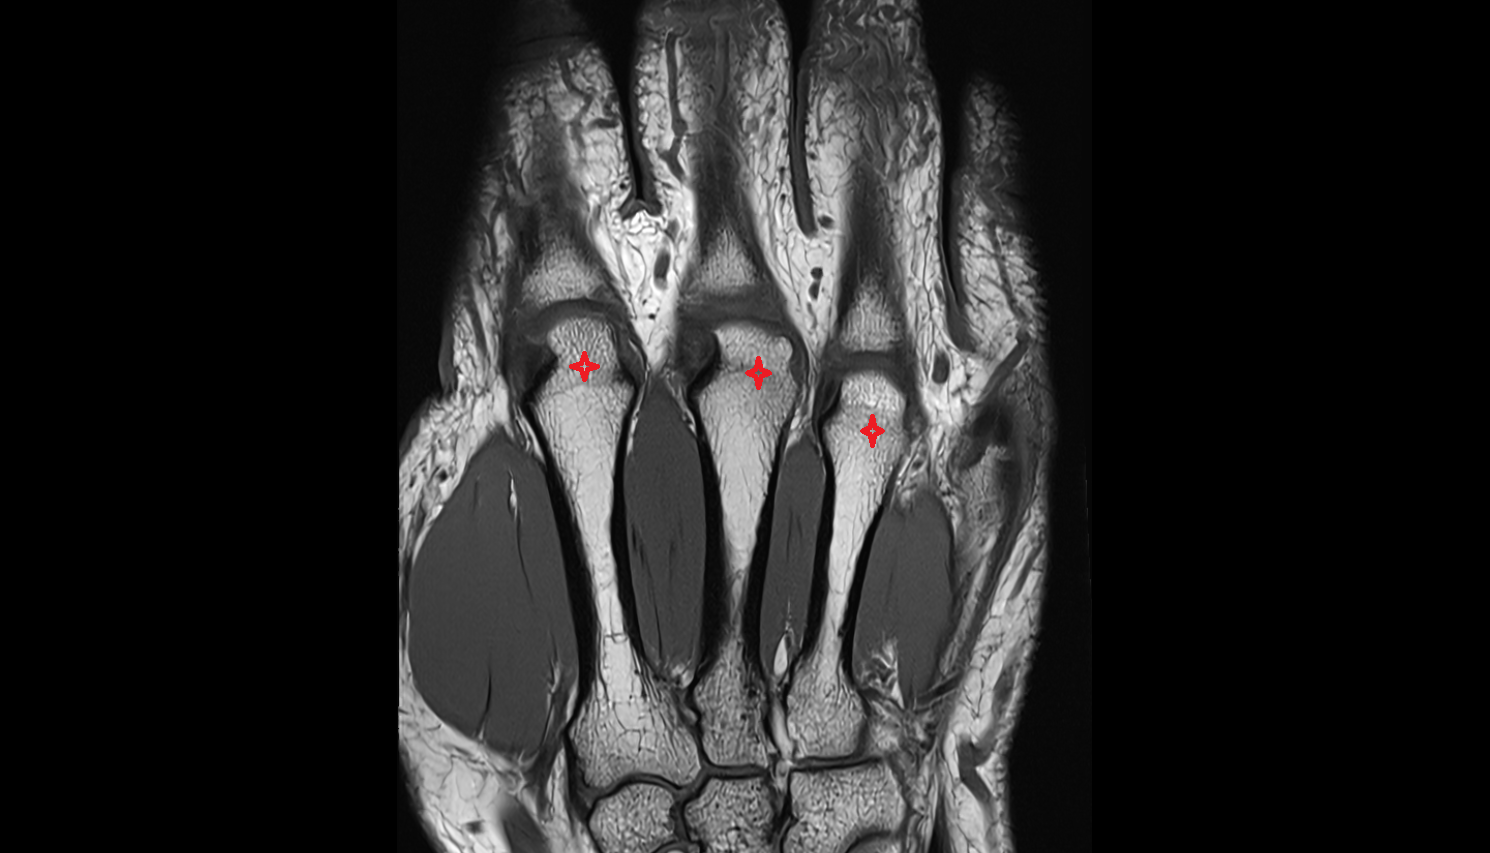

- Cubital tunnel